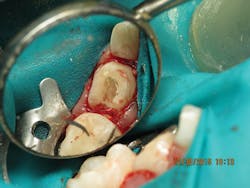

MTA pulpotomy using NuSmile NeoMTA